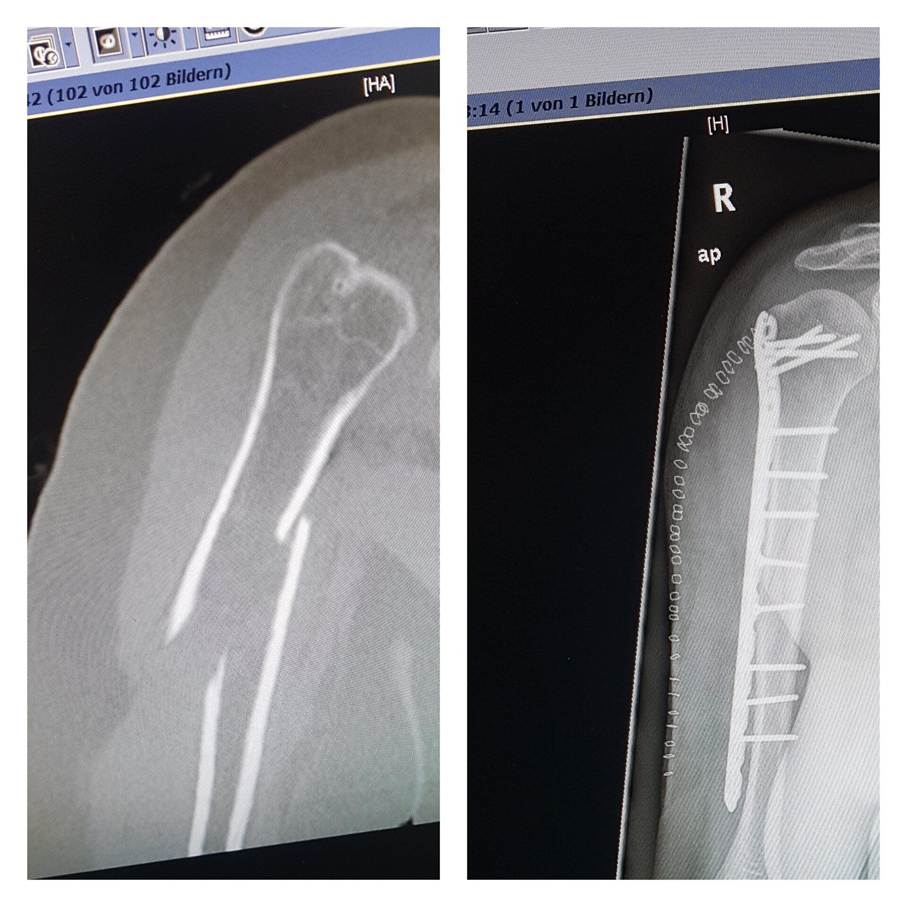

Seither ist vieles passiert, der Camino, mein Unfall im Januar 2020 und die C…Zeit haben mich sehr verändert. Doch die Faszination, die Magie des Jakobsweges haben mich nicht mehr losgelassen. Als ich im Januar 2020 meinen 50. Geburtstag unter Schmerzen und vielen Schmerzmittel im Krankenhaus und abends dann in meinem eigenen Bett feiern durfte, wobei du dir denken kannst, dass da nichts mit feiern war, gab mir der Gedanke an den Jakobsweg als Ziel emotionalen Halt.

Durch die C…. Geschichte und dass ich Rücksicht nehmen wollte, habe ich in 2020 auf die Fortsetzung verzichtet. Auch war ich körperlich durch die OPs und die Schäden, die ich davon getragen hatte viel zu geschwächt. Bei der ersten OP kamen Keime in die Wunde, was zwei weitere OPs nach sich zogen. Bei der dritten wurde mir noch ein Nerv im Arm verletzt und die Ärzte spielten es herunter, es könne nichts sein, ich wäre ebne etwas empfindlicher nach den ganzen OPs, Narkosen und Medikamenten. Eine Reha oder Nachsorge, gab es auch nicht, denn es war inzwischen der erste Lockdown.

Ein Arzt den ich dann doch noch nötigte, mich und meine Schmerzen ernst zu nehmen, meinte nach der Untersuchung: „Frau Steeg, orthopädisch ist alles o.k., die haben Ihnen in der Tat einen Nerv verletzt, das tut mir leid für Sie. Sie werden ihren Arm nie wieder so wie früher bewegen und nutzten können. Auch, weil die Ihnen so viel an Muskel- und Gewebemasse entfernt haben.“

Genau so ist es, ich bin nicht meine Krankheit und meine Krankenakte. Nur weil ein Arzt zu mir sagt, dass ich den Arm nie wieder wie früher bewegen kann, muss ich ihm noch lange nicht den Glauben schenken. Es mag vielleicht seine Wahrheit sein, aber nicht die meinige. Ab da ließ ich tagsüber die Opiate weg, um wieder klarer denken zu können. Dann stellte ich mir selbst all die Fragen, die ich sonst meinen Coaching-Klienten stellen würde. Vor allem suchte ich bei Dr. Google nach Hilfen und Lösungen, wie ich mich, meinen Arm und mein Leben wieder in den Griff bekommen kann. Mit vielen kleinen einfachen Übungen lernte ich zwar unter Schmerzen, aber immerhin meinen Arm und die Hand wieder zu bewegen. Stück für Stück.